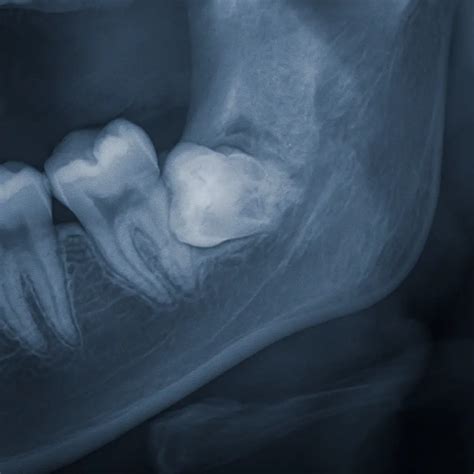

Why Wisdom Teeth are Prone to Infection

The anatomy of the wisdom tooth is the primary culprit behind these infections. Because they are the last teeth to emerge, they often encounter a crowded dental arch. This leads to impaction, where the tooth grows at an angle or fails to break through the gum line completely. This creates a small flap of gum tissue known as an operculum. Food debris and plaque easily hide beneath this flap, and because it is located so far back in the mouth, it is notoriously difficult to clean with a standard toothbrush or floss.

A dental professional is the only one who can definitively diagnose an infected wisdom tooth through a clinical examination and X-rays. If you notice the signs wisdom tooth infection, your dentist will likely assess whether the tooth needs to be extracted or if the infection can be managed with professional cleaning and antibiotics. In many cases, if a wisdom tooth has become infected once, it is highly likely to happen again. Extraction is frequently recommended as the permanent solution to remove the source of the recurring bacterial buildup and protect the surrounding healthy teeth.